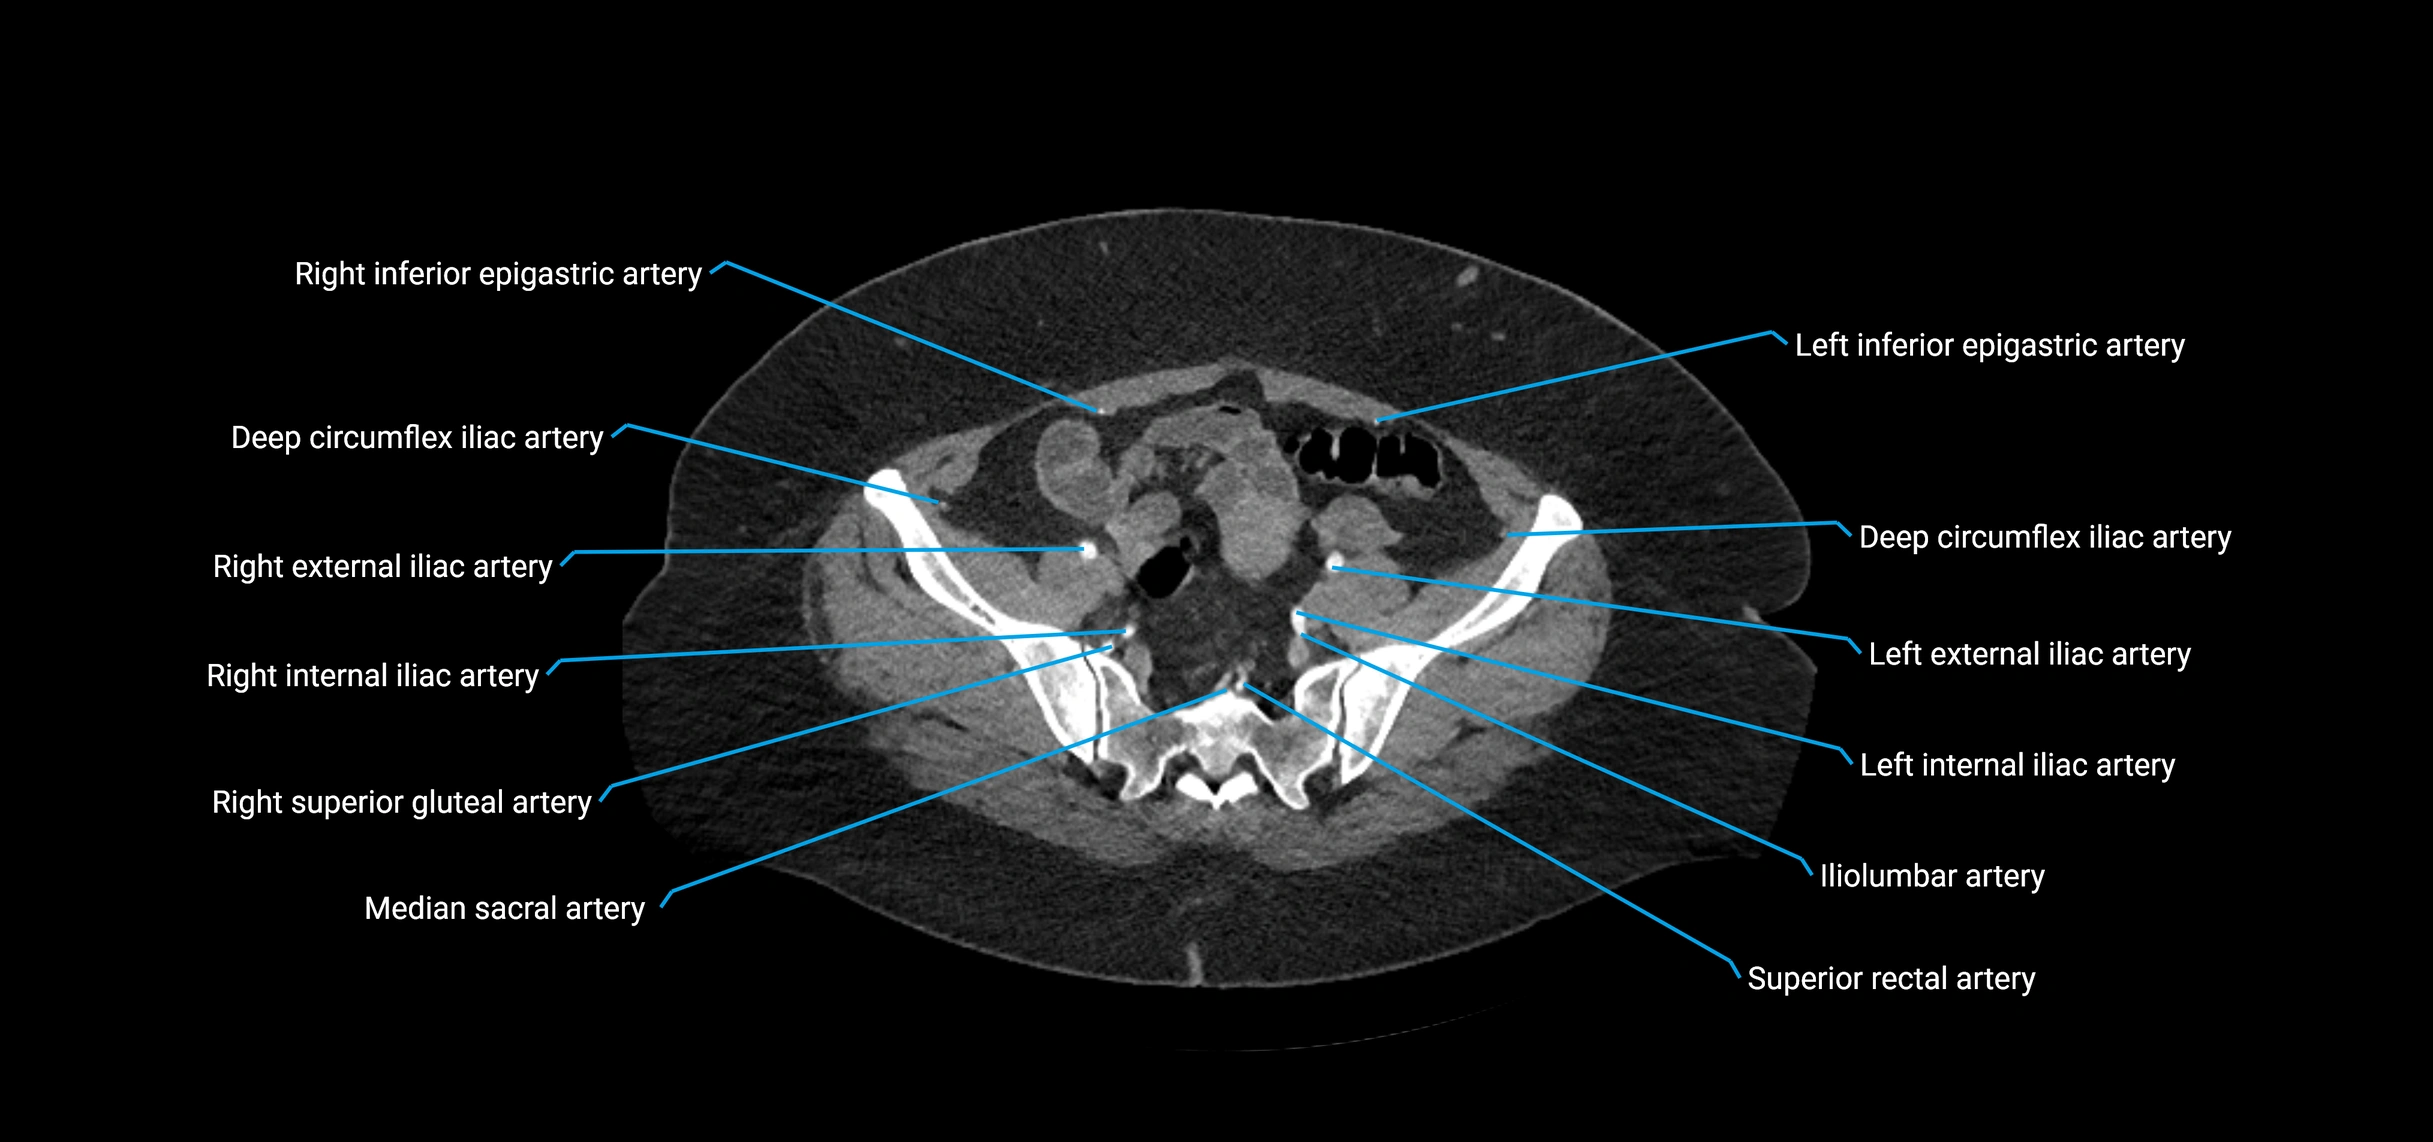

Contrast-enhanced CT (CTA):

• Gold standard for abdominal aortic imaging

• Provides excellent detail of lumen, wall, aneurysm, thrombus, and branch vessels

• Multiplanar and 3D reconstructions help in aneurysm measurement, stent graft planning, and dissection evaluation